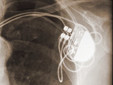

Se la diagnosi viene confermata ed il nostro segnale elettrico latita a fare il proprio dovere avremo bisogno di un pacemaker.

Mio padre ne ha messo giusto uno un paio di settimane fa ed ora sta benissimo (tocchiamo ferro)ed anche lui accusava questi sintomi: faceva fatica a fare le scale (fiatone, diceva lui), nausea, improvvisa sensazione di vuoto allo stomaco..il tutto cessava se immediatamente si fermava… Ansia? Stress? Cattiva digestione??? No.. misurandosi DA SOLO la pressione ha visto che i battiti cardiaci, che normalmente devono essere almeno 60, erano scesi a 35: troppo pochi, non credete amici miei?? Quindi immediata visita al pronto soccorso, elettrocardiogramma, ricovero in cardiologia per immediato posizionamento di pacemaker e dimissioni dopo un paio di giorni . Dopo alcune visite di controllo e la rimozione dei punti la vita riprende normalmente.. Bisogna solo abituarsi al nuovo amico con relativo bozzo sotto la clavicola sinistra (nella maggior parte dei casi,ma posizionato talvolta anche a destra)…. se si pensa che è un salvavita, alla sera quando si va a dormire gli si dà una carezza…..